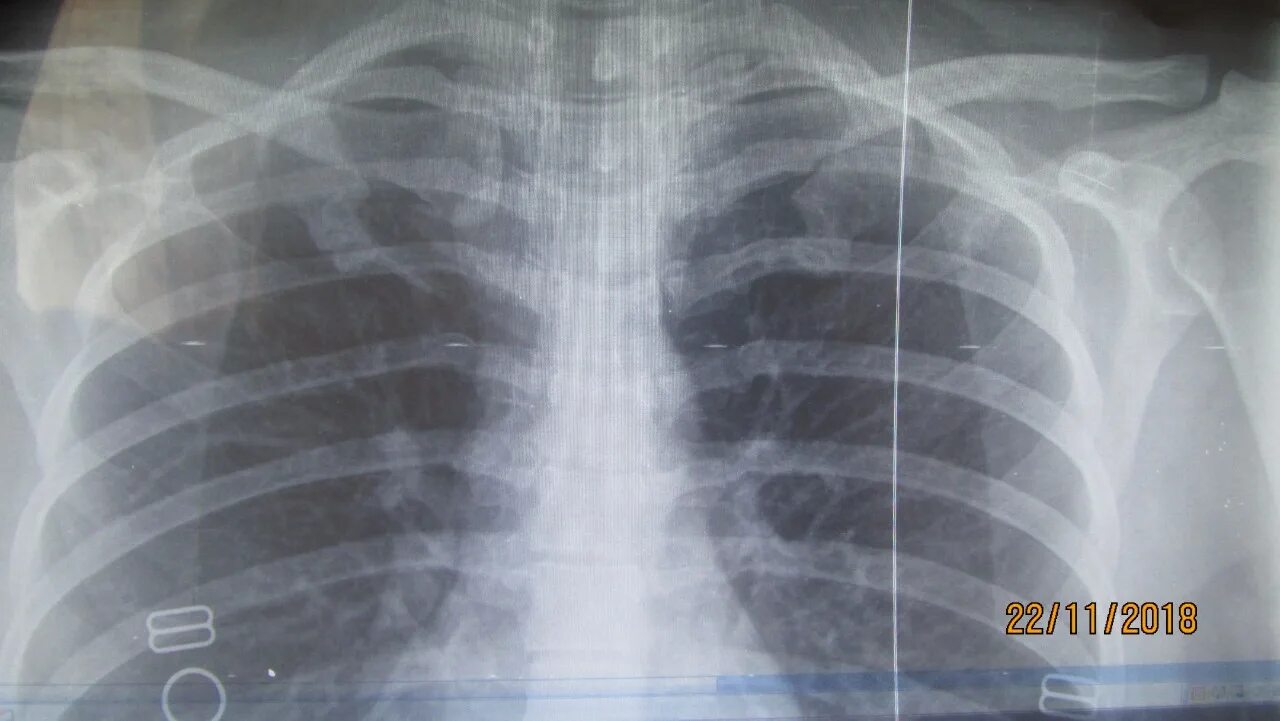

Синдром титце